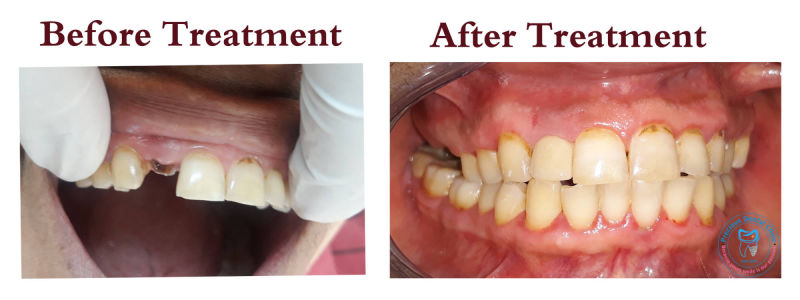

Post and Core

Post and Core Ulcer